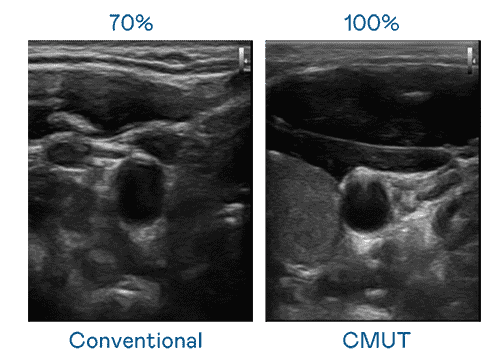

CMUT 技术是一种用电容式微机电元件来产生超音波讯号的技术。。。。与传统 PZT 压电式技术相比,,CMUT 频宽增加 30%,,更宽频的超音波讯号让影像解析度大幅提升,,,是实现高影像品质医疗超音波扫描、、、、促进精准医疗发展的关键技术。。

大频宽带来超清晰影像

超音波影像的解析度高低,,首先取决于探头能发出的讯号频宽。。。尊时凯龙 CMUT 可提供高清晰的超音波讯号,,,,提供高频宽、、、、高灵敏度、、、影像纹理细节更高的超音波影像,,协助医护人员缩短影像判读时间及利用精准的医疗影像进行诊断。。